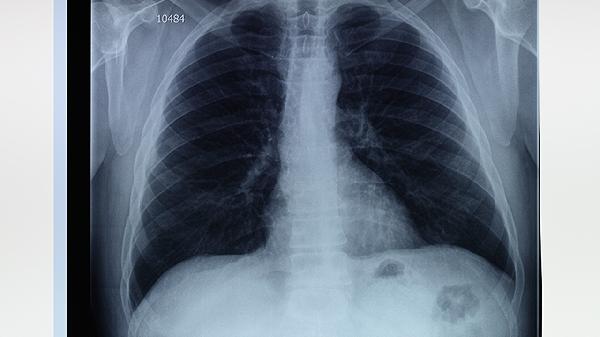

肺气肿、肺大泡合并肺动脉高压属于较严重的呼吸系统疾病组合,其严重程度主要与肺功能损害程度、并发症风险及肺动脉压力水平相关。病情发展可能影响气体交换效率,增加右心负荷,甚至导致呼吸衰竭或肺源性心脏病。

肺气肿导致肺泡壁破坏,肺大泡形成后进一步减少有效呼吸面积,二者协同作用会显著降低肺的弥散功能和通气效率。患者常表现为活动后气促、血氧饱和度下降,严重时静息状态下也会出现呼吸困难。

长期缺氧引发肺血管收缩和重塑,使肺动脉平均压持续≥25mmHg。这会加重右心室后负荷,初期表现为代偿性心室肥厚,后期可能出现右心衰竭,伴随颈静脉怒张、下肢水肿等体循环淤血体征。